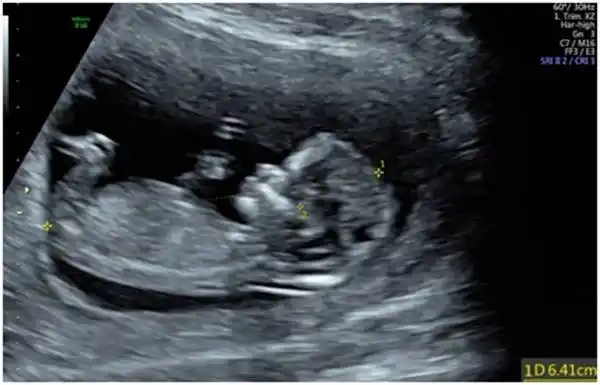

一口气教您读懂超声nt报告_胎儿_筛查_检查

23周胎儿图